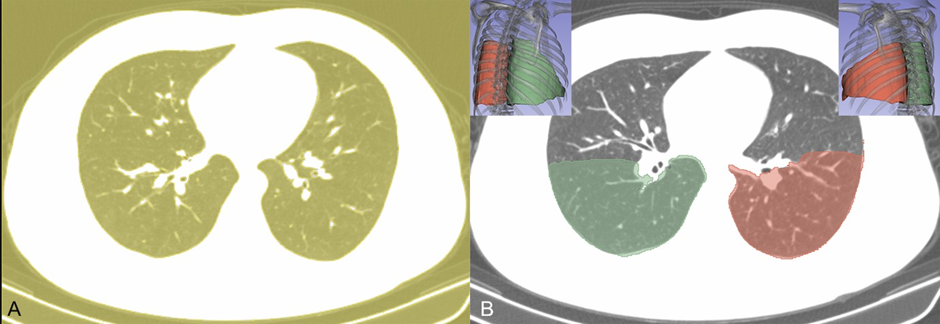

The data of visually negative CT scan were transferred to an offline workstation, and semi-automated parenchyma volume segmentation and fully automatic volumetric density calculations were performed using dedicated software (3D Slicer v4.10.2 software, http://www. slicer.org). The lung lobe to be segmented was determined based on the positive finding at second CT scan (Figure 2 A and B). Three radiologists with 10 years of experience in thoracoabdominal radiology processed the data retrospectively and a consensus was reached. Lung segmentation was performed in two steps: First, a threshold function was applied and parenchyma with density between -500 and -1024 HU was selected (Figure 3A). This selection was used as masking, and then semiautomated tracing function was applied to each slice for the selection of the symmetric lung lobes separately (Figure 3B). While the level tracing method enabled the segmentation of the lung, the threshold function eliminated the pixels with high density from anatomical structures, such as vessels and bronchi. Volumetric density calculations were performed automatically for each lobe using the built-in segmentation statistics of the software.

Figure 3: Lung segmentation of the CT image of the patient in Figure 2. (A) An initial segmentation was applied with a density threshold function (between -500 and -1024 HU). (B) Later, a contour tracing method was used for the lobe segmentation to acquire volumetric data.